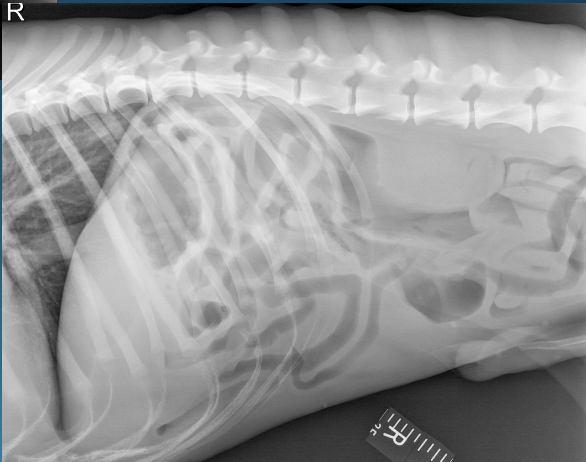

What is shown in these images?

normal abdomen and normal body wall in a dog